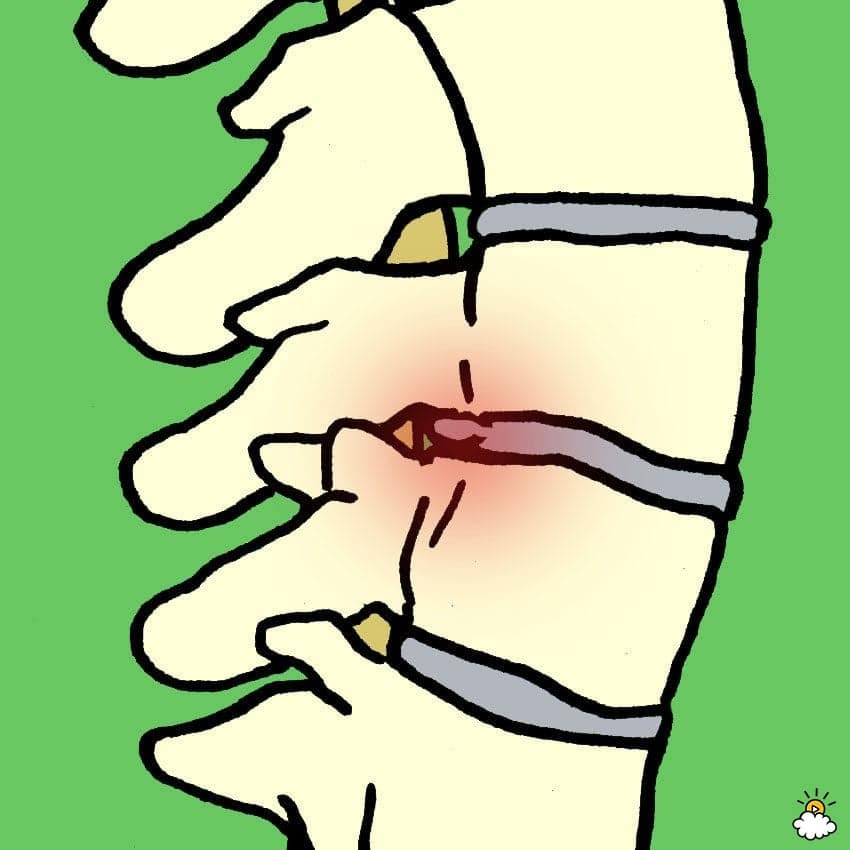

Τι είναι η δισκοπάθεια;

Η δισκοπάθεια εμφανίζεται όταν ο μαλακός ιστός που διαχωρίζει τους σπονδύλους σπάει, προκαλώντας πολύ πόνο και δυσφορία, σύμφωνα με τη Κλινική Μέιο.Αυτό μπορεί να συμβεί σε οποιοδήποτε μέρος της σπονδυλικής στήλης, όμως είναι συχνότερη η εμφάνισή του στη μέση (οσφυϊκή χώρα) ή τον αυχένα.